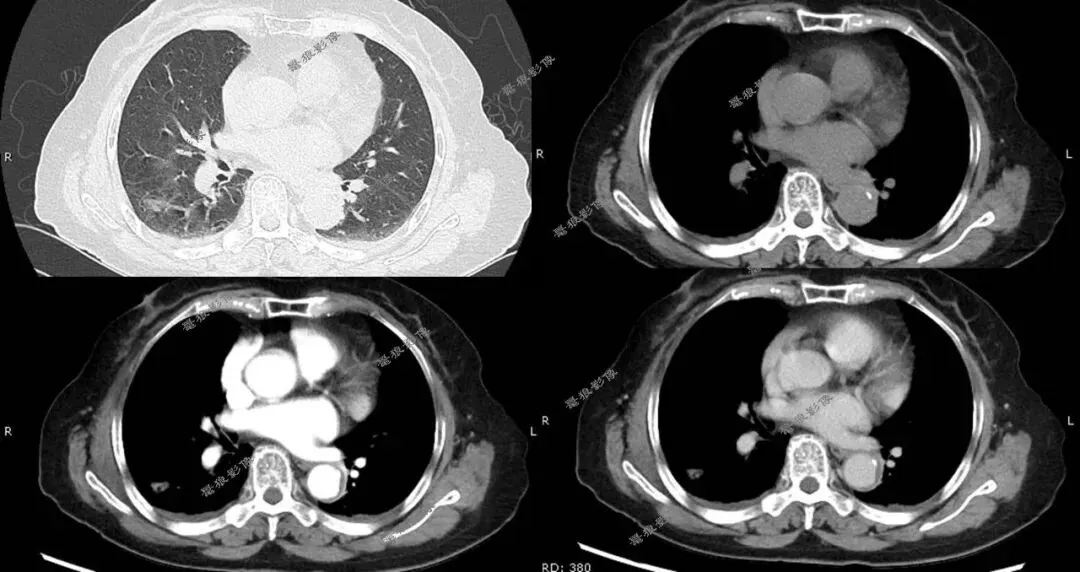

二、后行胸部CT平扫+增强(如下图):

胸部CT平扫+增强提示:

右肺下叶背段(IM118)见一浅分叶状实性结节,大小约为17mm×14mm,病灶边缘可见多发短毛刺,邻近斜裂稍凹陷,增强扫描病灶呈较明显不均匀强化。左前上纵隔见一类圆形软组织肿块,边界尚清,大小约69mm×44mm×51mm,密度较均匀,增强扫描病灶呈较均匀性轻度强化。

1.右肺下叶背段浅分叶状实性结节,考虑肺Ca可能性大,建议治疗后复查。

2.左前上纵隔软组织肿块,考虑胸腺瘤,必要时进一步检查以除外其它肿瘤性病变。